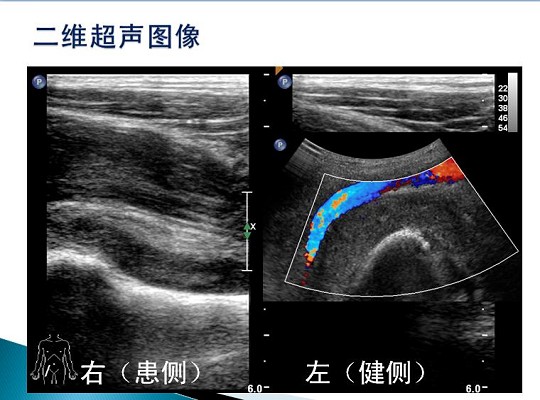

第三届中国超声造影大会病例大赛北医三院超声科获奖病例展示(三)